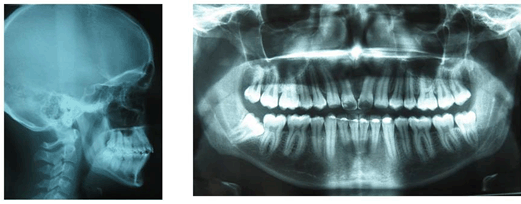

Treatment Results

By bringing the maxillary lateral incisors in place of central incisors and placing restoration on them with appropriate dimensions, the final result was esthetically and functionally acceptable (Figure 5) (Figure 6). All the treatment objectives were achieved and patient was pleased with the results.

Figure 6: Post-treatment lateral cephalogram and orthopantomogram.